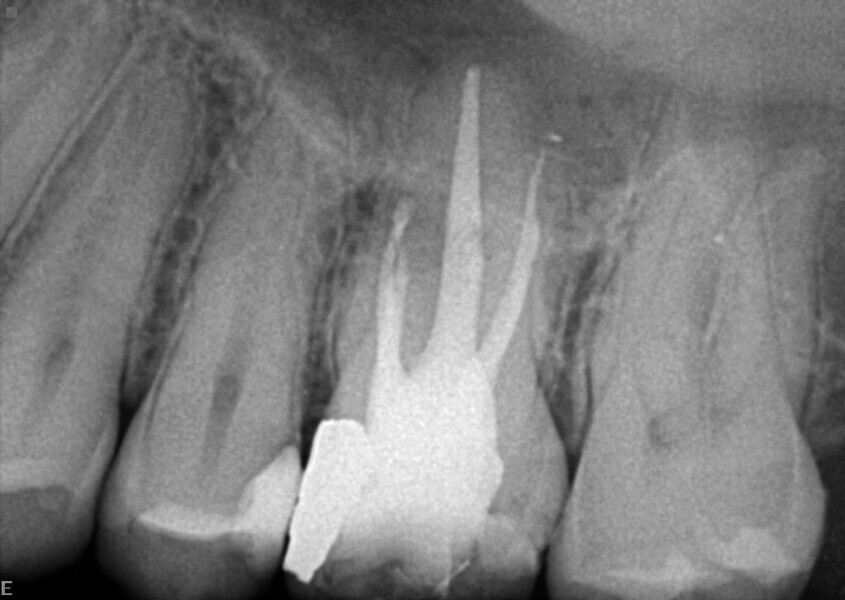

Maxillary sinus and root canal therapy complications